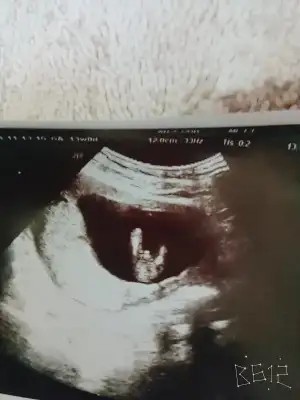

Valla benim 11 . Haftada doktorum kararsz kaldı ama dün devlette ikili test için gittim kız dedi ama yanındaki stajere sordu birde kız dimi diye saçma geldi bana emin olmayarak dedi çünkü benim içime erkek doğuyor ultrason resmine göre

• 20181105_171520.webp

20181105_171520.webp

28,6 KB · Görüntüleme: 80